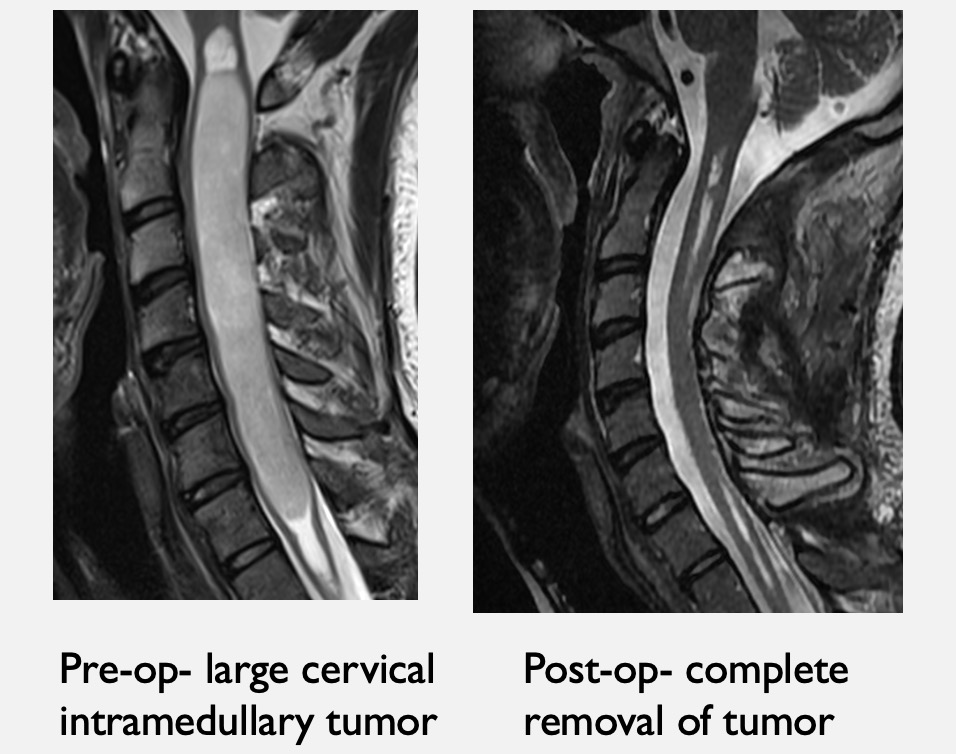

From www.paulcmccormick.com

Dr. McCormick presents at Neuroscience Grand Rounds on Spinal Tumors at Tufts Medical Spine Center From alleviating mild neck and back discomfort to performing minimally invasive spinal surgery, our spine care specialists are dedicated to helping you return to enjoying. Back and neck pain can range from mild aches to severe discomfort that can impact your quality of life. Pour mener à bien leurs travaux, les équipes de l'institut des sciences du vivant frédéric joliot. Tufts Medical Spine Center.